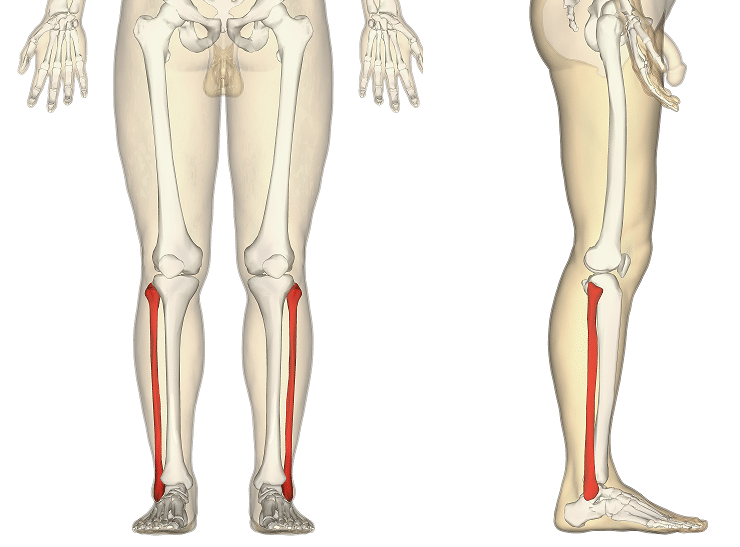

ফাইবুলা (pl.: fibulae বা fibulas) বা বাছুরের হাড় হল টিবিয়ার পার্শ্বীয় দিকে একটি পায়ের হাড়, যার সাথে এটি উপরে এবং নীচে সংযুক্ত থাকে। এটি দুটি হাড়ের মধ্যে ছোট এবং এর দৈর্ঘ্যের অনুপাতে, সমস্ত দীর্ঘ হাড়ের মধ্যে সবচেয়ে সরু। এর উপরের প্রান্তটি ছোট, টিবিয়ার মাথার পিছনের দিকে, হাঁটু জয়েন্টের নীচে এবং এই জয়েন্টের গঠন থেকে বাদ দেওয়া হয়। এর নীচের প্রান্তটি একটু সামনের দিকে ঝুঁকেছে, যাতে উপরের প্রান্তের সামনের সমতলে থাকা যায়; এটি টিবিয়ার নীচে প্রজেক্ট করে এবং গোড়ালি জয়েন্টের পার্শ্বীয় অংশ গঠন করে।